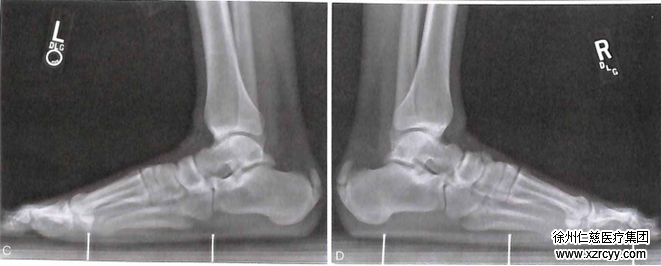

这类疾病常发生在运动员和体育爱好者身上,导致这类疾病发生的主要原因还是在于跟腱在反复奔跑和牵拉过程中造成的跟腱止点的变性损伤、脆弱,有时甚至会是断裂。

患者通常可以从跟腱炎中得到完全的恢复,但是这可能需要很长的时间,因为跟腱在每一步的行走中都会受到牵拉。活动状态的改变非常重要。在一般情况下,跟腱炎在经过一段时间的自我护理(例如休息、冰敷、服用非处方类镇痛药等) 后会得到改善。如果没有什么效果,应该来医院就诊。

betway在线登陆手足显微外科四病区除了采用常规的物理+药物+封闭等治疗方法外,对于那些情况严重的非手术治疗无效的患者,采用微创手术来解除患者病痛,通常可以让跟腱炎得到完全的恢复,欢迎广大患者朋友们来院咨询治疗。